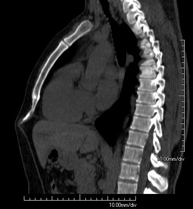

- Abdomen y pelvis- TC Abdomen Prueba diagnóstica que consiste en obtener imágenes del abdomen de alta definición anatómica (hígado, vesícula biliar, vía biliar, páncreas, bazo, estómago, intestinos, riñones, estructuras vasculares, vejiga, útero y ovarios, etc.) mediante el empleo de un equipo de TC (Tomografía Computarizada). Dichas imágenes se estudian posteriormente en una estación de trabajo que permite reconstrucciones bidimensionales en diferentes planos del espacio, y también reconstrucciones 3D (volumétricas). La mayoría de estudios requieren el empleo de contraste yodado para mejorar la definición de las imágenes. Prueba diagnóstica que consiste en obtener imágenes del abdomen de alta definición anatómica (hígado, vesícula biliar, vía biliar, páncreas, bazo, estómago, intestinos, riñones, estructuras vasculares, vejiga, útero y ovarios, etc.) mediante el empleo de un equipo de TC (Tomografía Computarizada). Dichas imágenes se estudian posteriormente en una estación de trabajo que permite reconstrucciones bidimensionales en diferentes planos del espacio, y también reconstrucciones 3D (volumétricas). La mayoría de estudios requieren el empleo de contraste yodado para mejorar la definición de las imágenes.

- TC Abdominopélvico Prueba diagnóstica que consiste en obtener imágenes bi y tridimensionales del abdomen y de la pelvis de alta definición anatómica (estructuras óseas, estructuras vasculares, hígado, páncreas, vesícula biliar, riñones, glándulas suprarrenales, bazo, intestino delgado y grueso, vejiga, útero y ovarios, próstata y vesículas seminales, uréteres, etc.) mediante el empleo de un equipo de TC (Tomografía Computarizada). La mayoría de estudios requieren el empleo de contraste yodado. Prueba diagnóstica que consiste en obtener imágenes bi y tridimensionales del abdomen y de la pelvis de alta definición anatómica (estructuras óseas, estructuras vasculares, hígado, páncreas, vesícula biliar, riñones, glándulas suprarrenales, bazo, intestino delgado y grueso, vejiga, útero y ovarios, próstata y vesículas seminales, uréteres, etc.) mediante el empleo de un equipo de TC (Tomografía Computarizada). La mayoría de estudios requieren el empleo de contraste yodado.